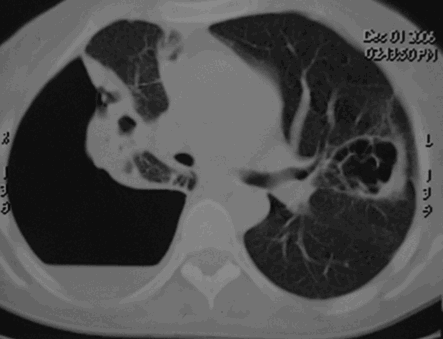

Эмпиема плевры